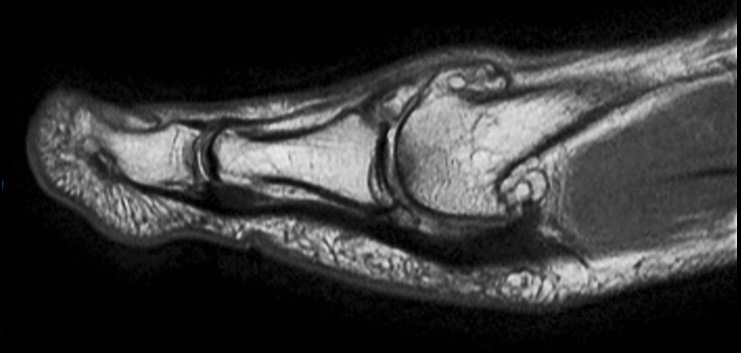

Coronal PDw mDIXON TSE  (water only)